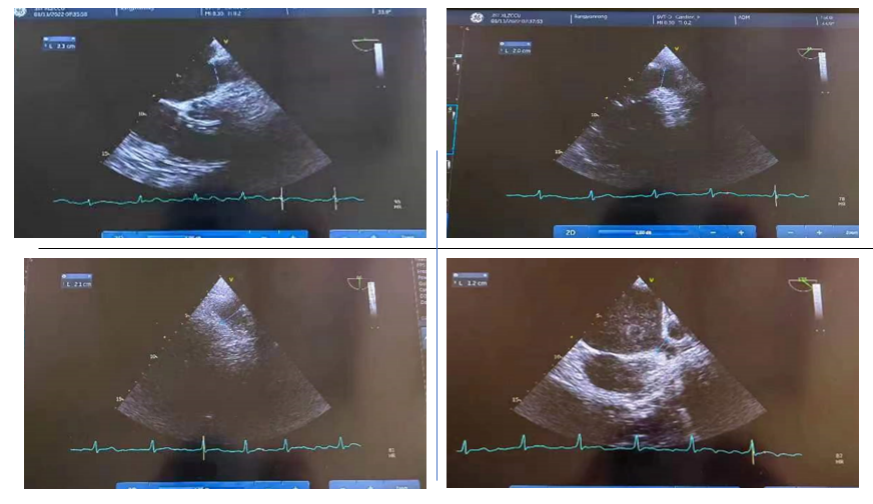

术前左房-肺静脉CT显示心耳结构三维重建模型,确定左心耳呈“风向标”形态。

术前经食道超声检查:在0⁰、45⁰、90⁰以及135⁰评估左心耳口部尺寸,预估选用的封堵器型号。